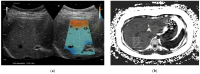

We investigated the feasibility of ultrasound attenuation imaging (ATI) for assessing pediatric hepatic steatosis. A total of 111 children and adolescents who underwent liver ultrasonography with ATI for suspected hepatic steatosis were included. Participants were classified into the normal, mild, or moderate−severe fatty liver group according to grayscale US findings. Associations between clinical factors, magnetic resonance imaging proton density fat fraction, steatosis stage and ATI values were evaluated. To determine the cutoff values of ATI for staging hepatic steatosis, areas under the curve (AUCs) were analyzed. Factors that could cause measurement failure with ATI were assessed. Of 111 participants, 88 had successful measurement results. Median ATI values were significantly increased according to steatosis stage (p < 0.001). Body mass index (BMI) was a significant factor for increased ATI values (p = 0.047). To differentiate fatty liver from normal liver, a cutoff value of 0.59 dB/cm/MHz could be used with an AUC value of 0.853. To differentiate moderate to severe fatty liver from mild fatty liver, a cutoff value of 0.69 dB/cm/MHz could be used with an AUC value up to 0.91. ATI can be used in children as an effective ultrasonography technique for quantifying and staging pediatric hepatic steatosis.